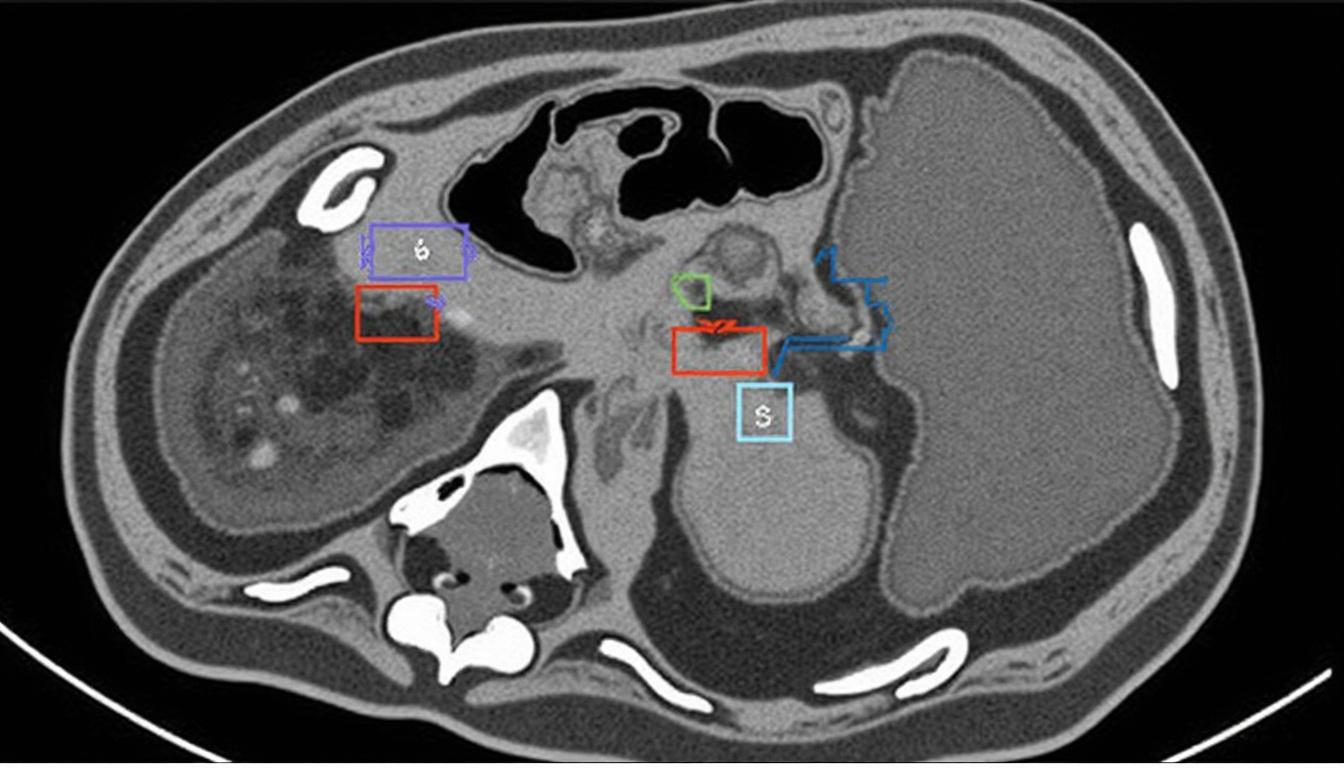

Au niveau morphologique, l’échocardiogramme met en avant un épaississement important et un excès de tissu valvulaire, souvent bilatéral. Le déplacement supérieur à 2 mm des feuillets mitraux en systole dans l’oreillette gauche est un critère incontournable. Cet examen évalue également la présence d’une disjonction annulaire mitrale, qui peut passer inaperçue sans Doppler tissulaire spécialisé.

Lorsque les données échographiques sont insuffisantes, notamment pour mieux caractériser la fibrose myocardique et les anomalies tissulaires, l’imagerie par résonance magnétique cardiaque (IRM) se révèle précieuse. Elle permet de détecter le rehaussement tardif évoquant une fibrose focale des muscles papillaires ou de la paroi ventriculaire, suspectée comme source d’instabilité électrique.